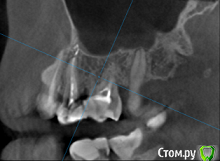

татьяна tat Опубликовано 4 сентября, 2016 Автор Поделиться Опубликовано 4 сентября, 2016 (изменено) скажите пожалуйста...по кт тоже видно ,что каналы не пролечены? Изменено 4 сентября, 2016 пользователем татьяна tat Ссылка на комментарий

Beznika Опубликовано 8 сентября, 2016 Поделиться Опубликовано 8 сентября, 2016 на 5 ке материал вывели за апекс. резекцию возможно придётся делать верхушки корня... + карман у вас есть за 6кой. а так всё равно перелечивать надо... масса пористая в каналах и не гомогенная. (не однородная) Ссылка на комментарий

татьяна tat Опубликовано 8 сентября, 2016 Автор Поделиться Опубликовано 8 сентября, 2016 (изменено) на 5 ке материал вывели за апекс. резекцию возможно придётся делать верхушки корня... + карман у вас есть за 6кой. а так всё равно перелечивать надо... масса пористая в каналах и не гомогенная. (не однородная) в каком случае мне грозит резекция? и что с карманом делать?может на срезах так видно...но врач оч. хорошей клиники,на очном приеме,смотря на компьютере кт,сказала,что каналы пролечены на 5+.....не считая того,что немного выведено материала Изменено 8 сентября, 2016 пользователем татьяна tat Ссылка на комментарий